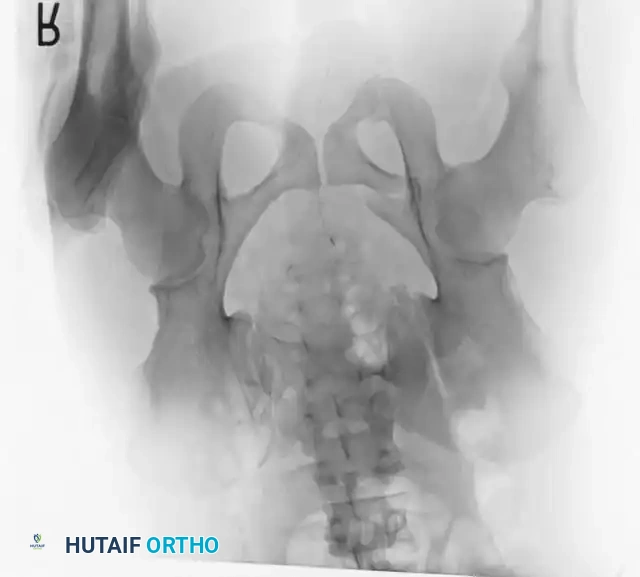

Radiographic Evaluation

Standard evaluation begins with an Anteroposterior (AP) pelvis radiograph. However, definitive surgical planning requires specialized views and advanced imaging.

• Inlet View: Directed 45 degrees caudad. Best evaluates anterior-posterior translation, internal/external rotation, and sacral impaction.

• Outlet View: Directed 45 degrees cephalad. Best evaluates vertical translation and sacral foraminal anatomy.

• CT Scan: The gold standard for evaluating posterior ring injuries, sacral dysmorphism, and preoperative planning for percutaneous fixation.